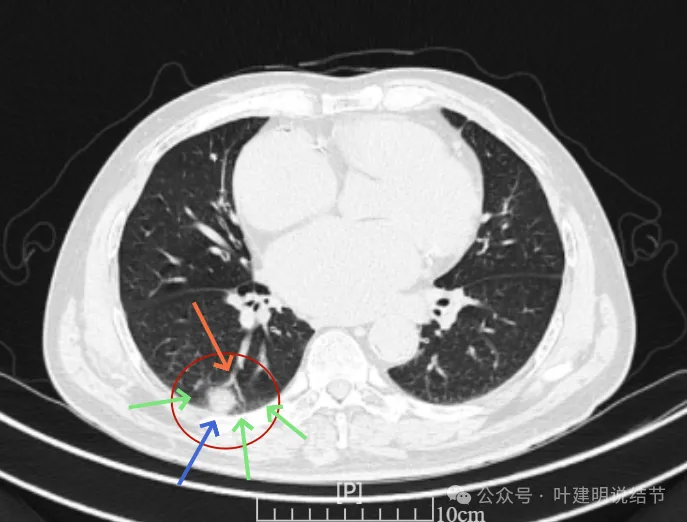

再看2024年6月时的影像:

右上没有明显变化,仍考虑良性可能性大。

左下也考虑良性,与2022年无明显变化。

右下新增病灶,混合密度,整体轮廓较清,瘤肺边界欠清。

有小血管进入,边缘毛糙。

局部有毛刺,但不够锐利;病灶感觉有一层晕似的,邻近胸膜下也有淡磨玻璃影。

实性密度为主,周围少许很淡的磨玻璃影。

边缘不平有毛刺,但不锐利;贴着胸膜但无明显牵拉。局部表面有浅分叶似的,但总体膨胀感不够。

病灶表面不光滑,边上有晕,邻近有淡磨,贴着胸膜无牵拉。

病灶边缘欠清晰,瘤肺边界稍模糊。较宽的基底贴着胸膜。

病灶有血管进入,有浅分叶,实性为主,邻近胸膜有片状淡磨玻璃影,近胸膜无牵拉。但有一定膨胀性。

病灶实性,与血管关系较为密切。

血管走向病灶,但似乎没有被病灶影响,有向内侧的分支甚至没有哪怕一点凹向病灶侧。整体显得偏模糊。

边缘区域杂乱,边糊。